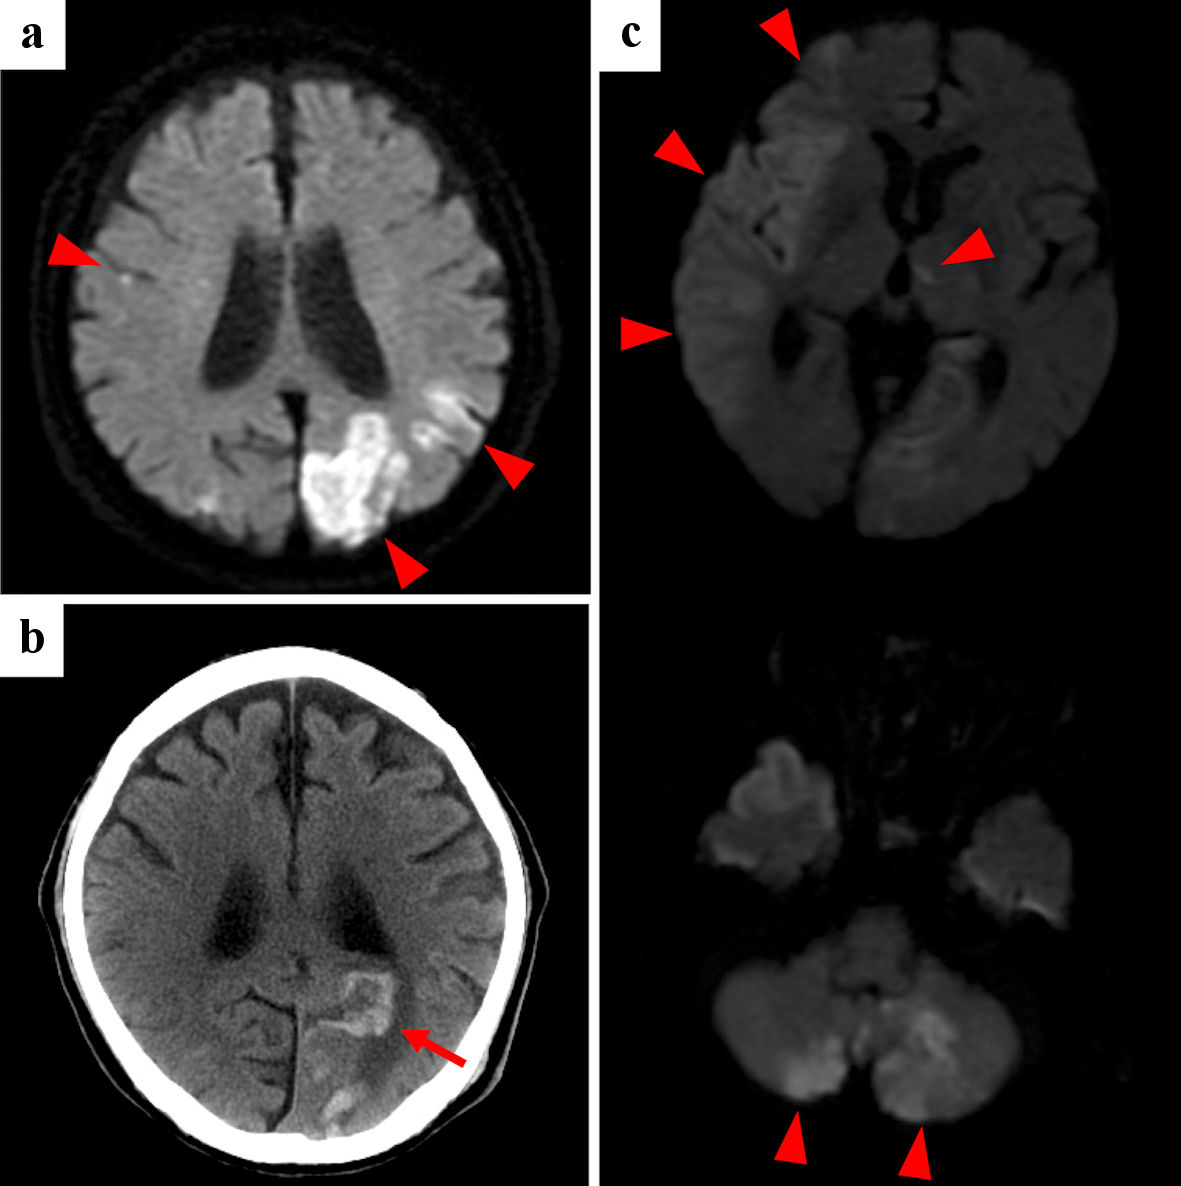

Multiple and coincidental cerebral infarctions in bilateral multiple vascular territories were the most frequent radiological features shown by brain MRI (n = 9). As representative cases, the images of cases 1and 2 are shown in Figures 1 and 2, respectively. Nine had neurological symptoms at the time of the initial cerebral infarction, while one was asymptomatic.

![]() Click for large image | Figure 2. Case 2: brain diffusion-weighted MRI (a, c) and CT (b) of initial cerebral infarctions (a), hemorrhagic infarction (b) and recurrent cerebral infarctions (c). Red arrowheads point cerebral infarctions, and red arrow points hemorrhagic infarction. MRI: magnetic resonance imaging; CT: computed tomography. |

Recurrent cerebral infarctions were observed in six patients, all within 50 days. Five had recurrence despite anticoagulation therapy. Among the four patients who started and continued heparin at the initial onset, one had a recurrence. On the other hand, among the other four patients whose initial treatment was anticoagulants other than heparin or who did not continue heparin, all four had recurrences. Two patients did not receive anticoagulants at the initial onset because of their poor general condition. While heparin was used for initial treatment in four patients, it was used in seven patients during the course of treatment. Moreover, three patients were discharged using self-injection of subcutaneous heparin calcium at home. Since low-molecular-weight heparin has not been approved by Japanese medical insurance for the treatment of cerebral infarction, we used intravenous unfractionated heparin or subcutaneous heparin calcium.